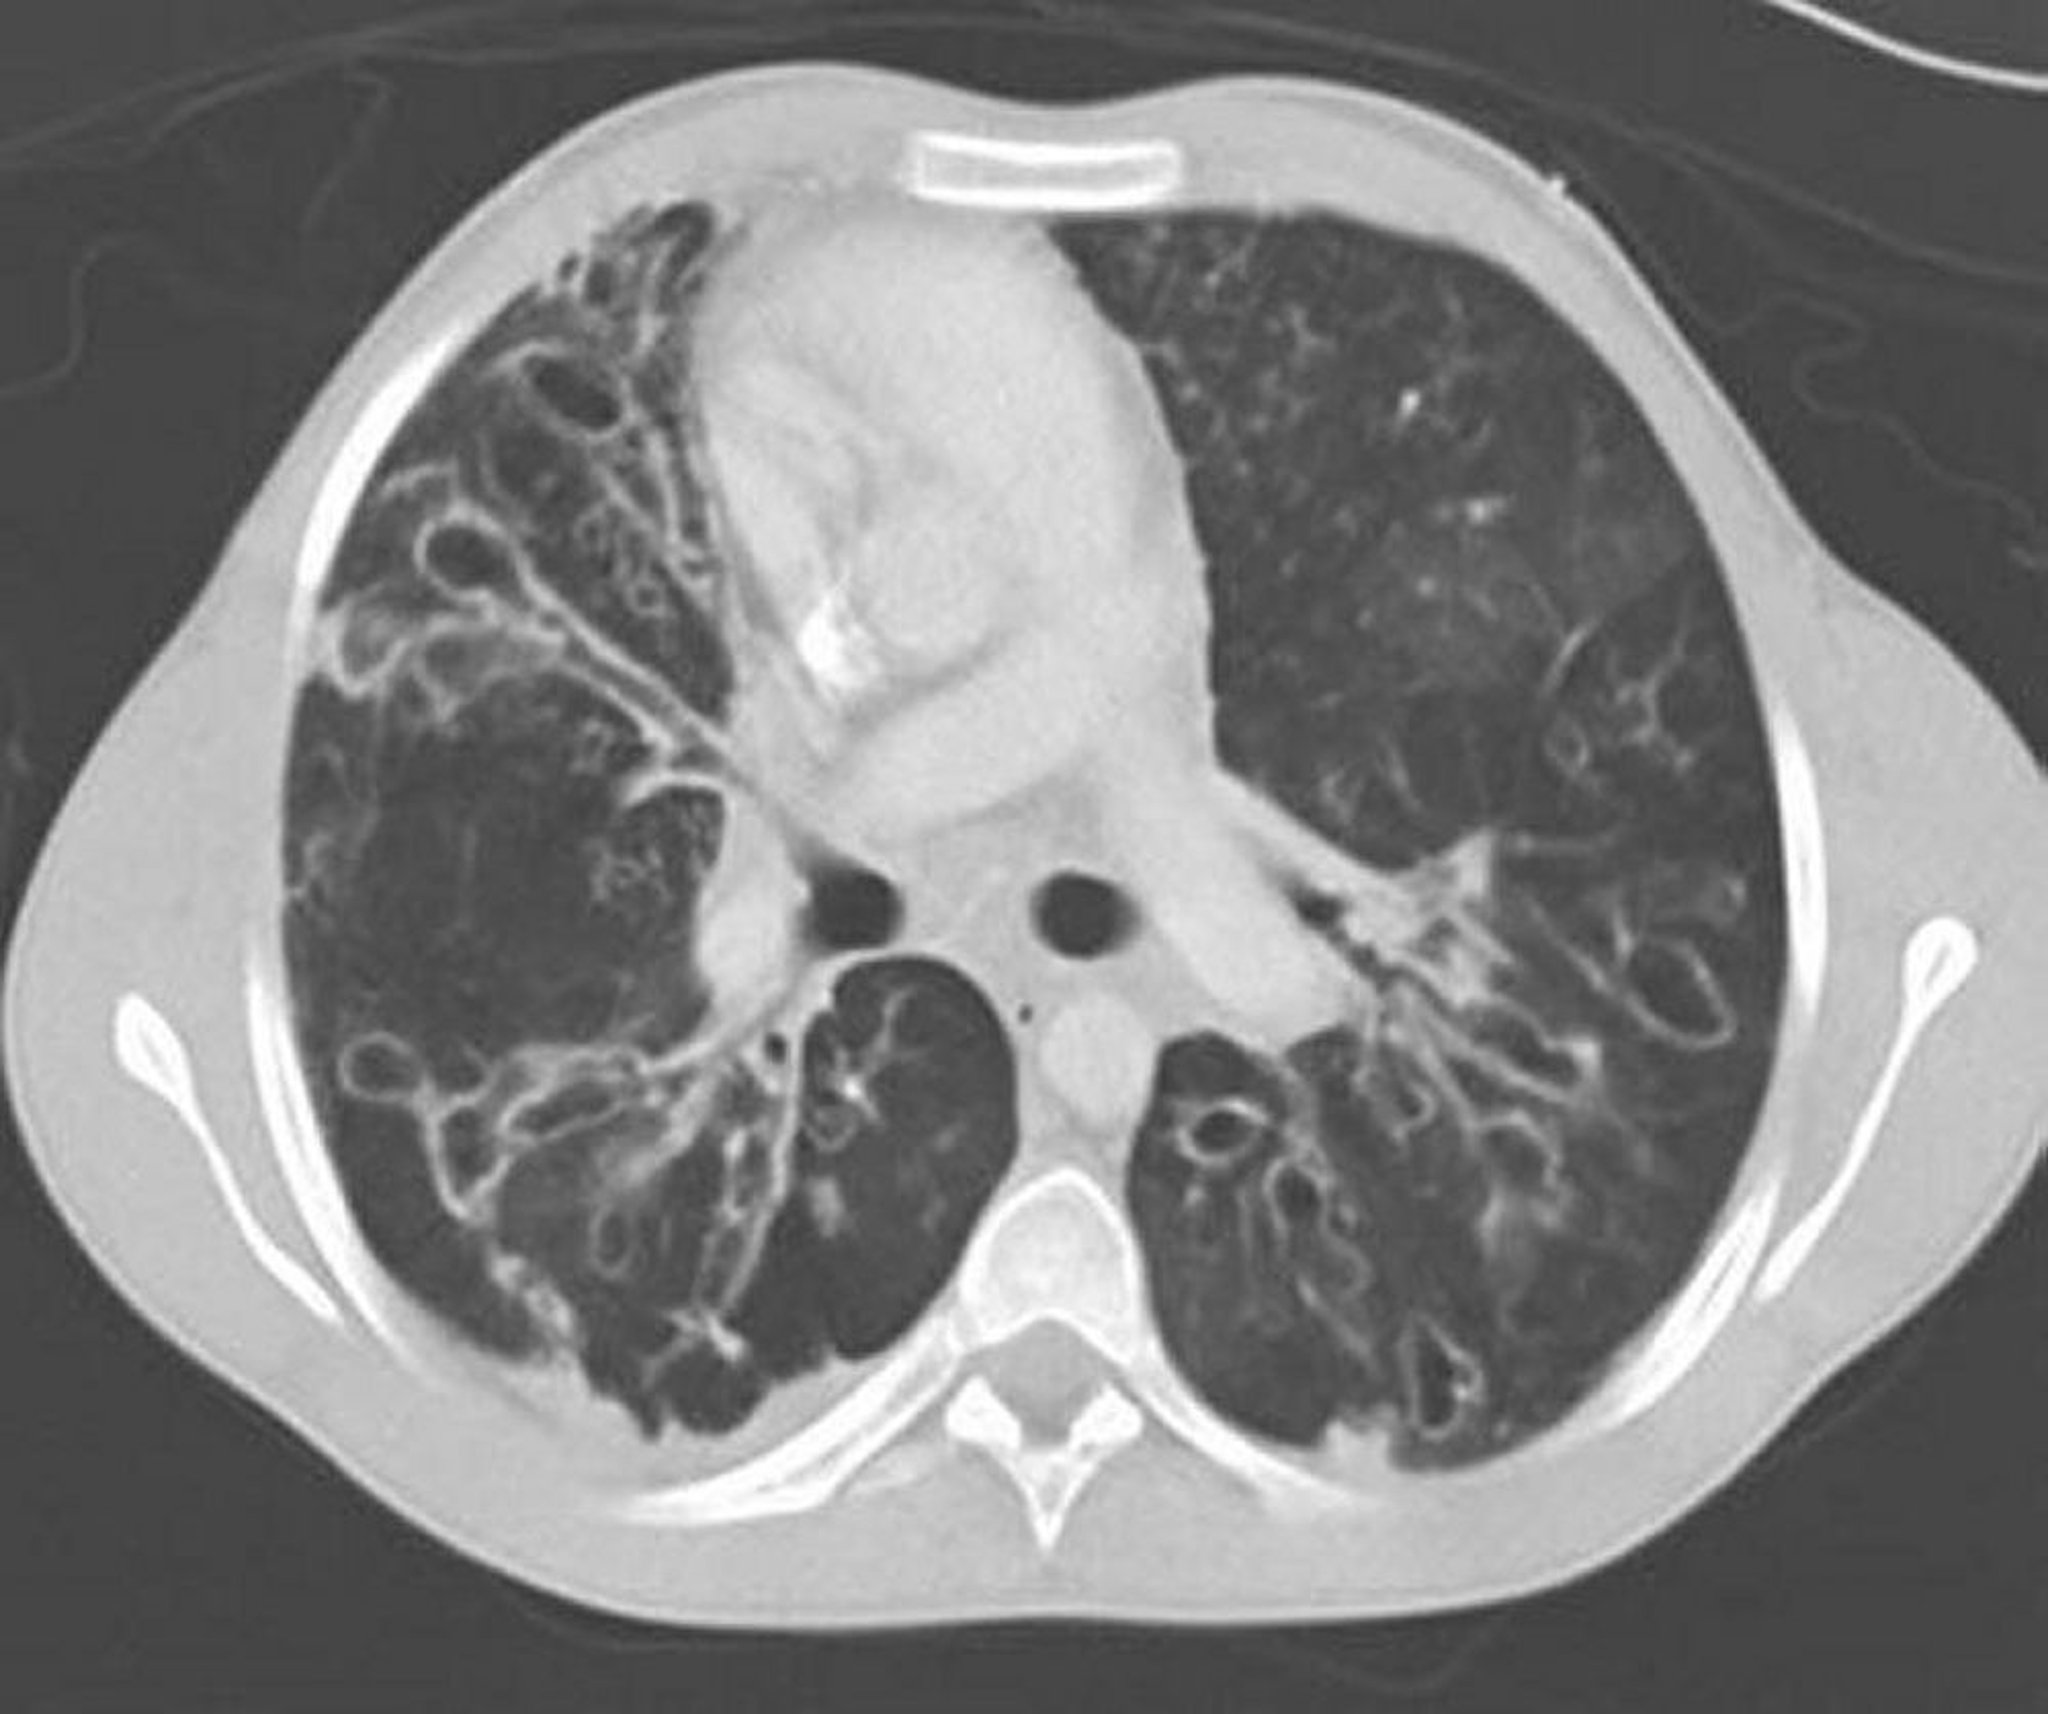

Bệnh do nấm aspergillus phế quản phổi dị ứng (giãn phế quản)

CT ngực có tiêm cản quang cho thấy giãn phế quản nghiêm trọng ở vùng thùy giữa với phế quản bị giãn rộng hoặc giãn và thay đổi dạng nang. Giãn đường thở đặc trưng bởi tỷ lệ đường thở so với mạch máu kế cận > 1.